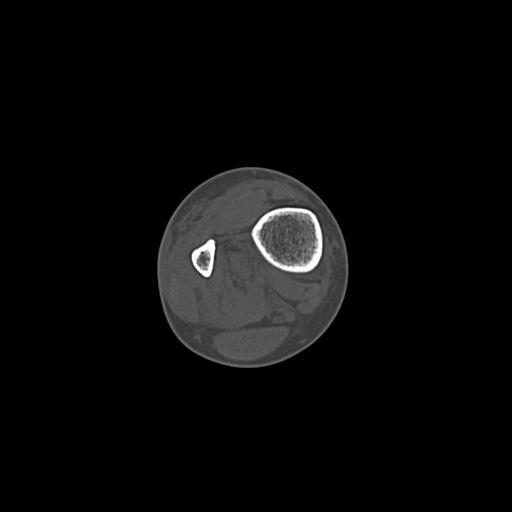

110211 1/6 1/8 左前腕 4R 15歳男性 橈骨骨幹部骨折